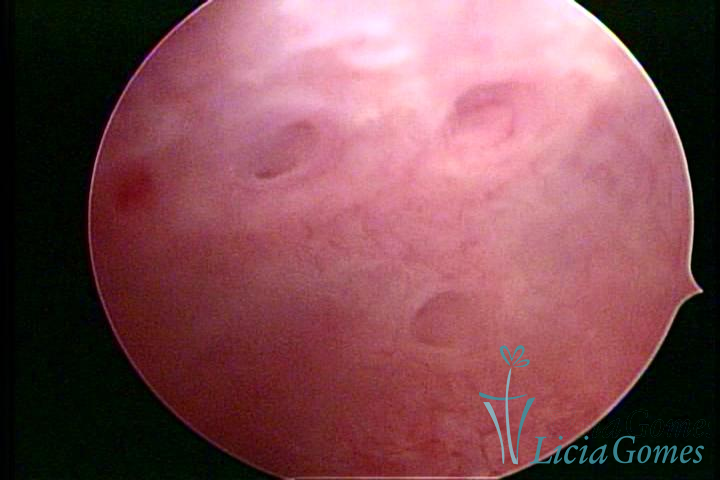

ADENOMYOSIS

The presence of endometrial tissue on the muscular layer of the uterus.

Video hysteroscopy allows diagnosing the lesions next to the superficial myometrial layers next to the endometrium, allowing the view of in situ, purplish, or chocolate brown lesions.